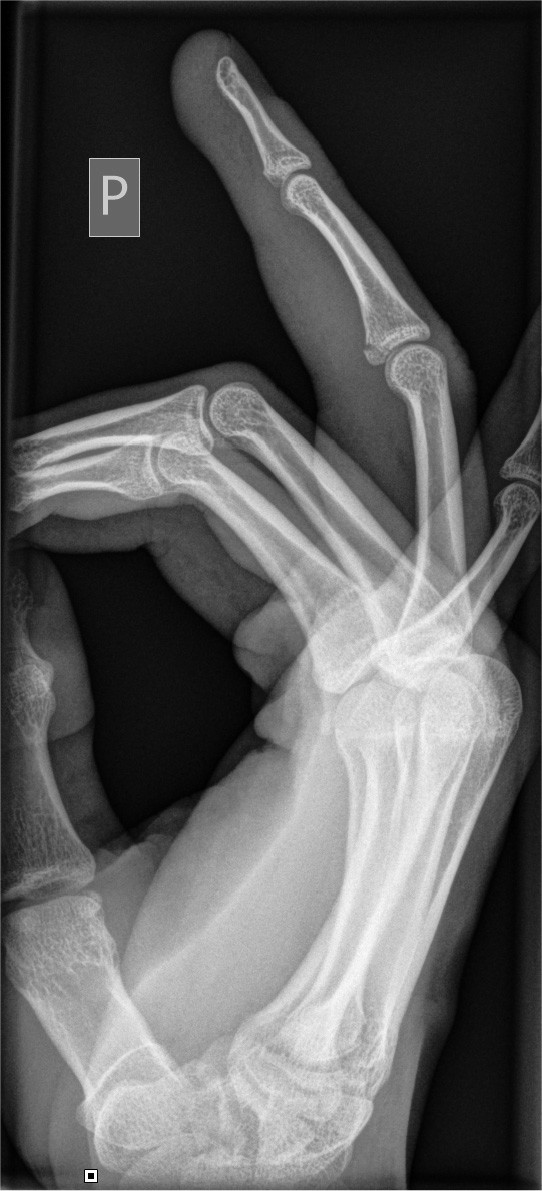

How it looks in practice

See how Carebot works in practice. Compare the image with AI and without AI.

Without Carebot

With Carebot

Overview of detected findings

Advanced analysis of skeletal and joint X-ray images. Detection of fractures in the axial skeleton, including typical pediatric fractures

Minor fractures

Major fractures

Bone dislocations